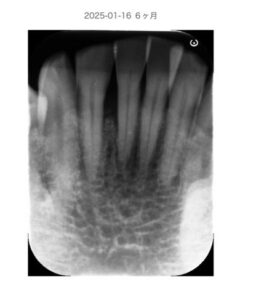

【症例例】咬合管理で安定したケース

50代 性別 男性

前歯に6mmの歯周ポケットと動揺あり。

歯周基本治療と咬合調整後

再生療法併用。

3ヶ月後にはポケットは3〜4mmに改善し、現在も安定しています。

After:

北新地での歯周病治療後の口腔内写真|炎症が改善し歯周組織が安定した状態